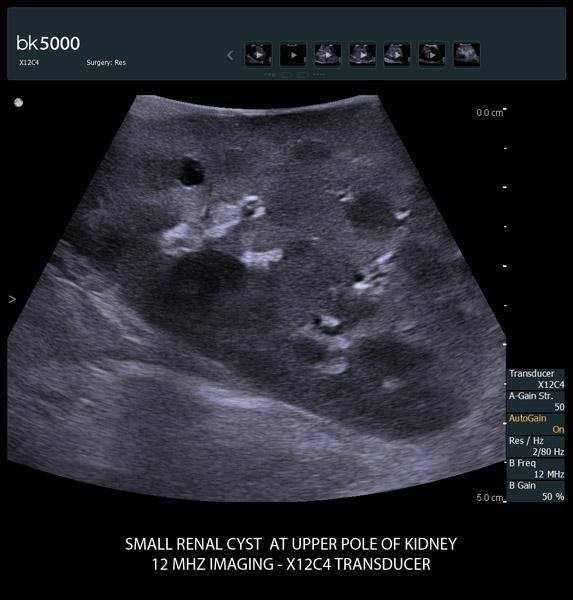

Ultrasound helps surgeons locate and visualize tumor margins, key arteries and other anatomical structures quickly and with greater precision during robotic-assisted surgeries.The bk5000 ultrasound system’s advanced technology can deliver exceptional images with very high contrast and spatial resolution, giving you the information you need to make critical decisions during surgery.

The unique Drop-In transducer enables access and visualization of complex organs and difficult-to-access anatomy in real-time. For example, in kidney navigation and difficult-to-access endophytic and exophytic tumors, the small, compact, curved linear array Drop-In transducer enables a wider field of view for faster examinations. The specially-designed fin grasped by the robotic arm ensures maximum control and organ contact so you can get the information you need.